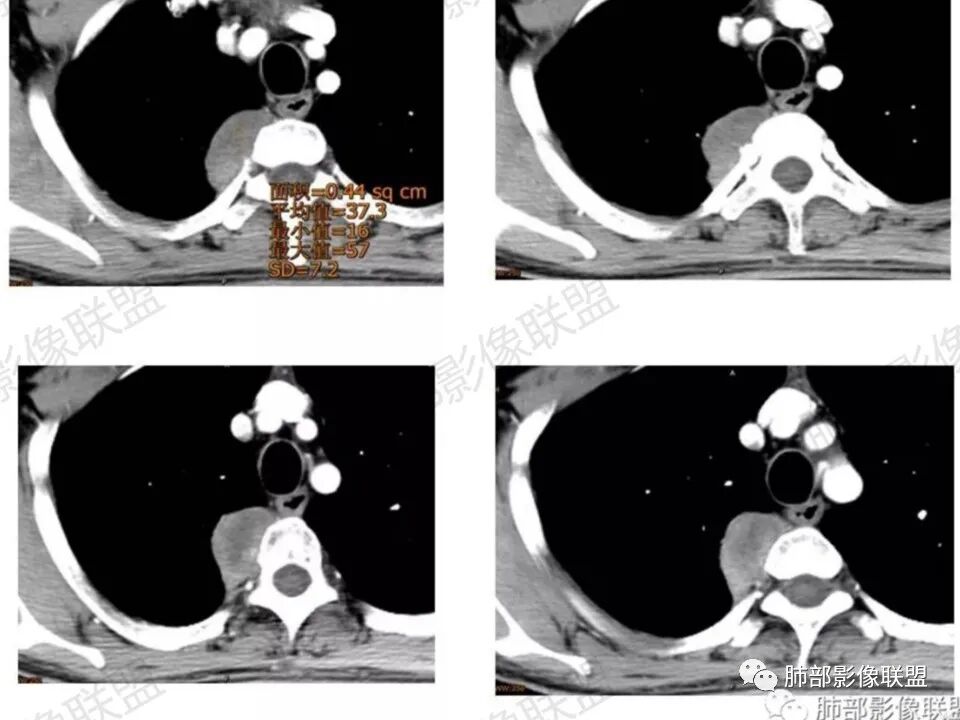

这个病例定位肺外没问题,病灶呈宽基底,见明显的胸膜掀起征,定位胸膜或右后纵隔来源,而且肿块提示肋间动脉穿行,脏层胸膜来源可能性不大(脏层胸膜由肺动脉及支气管动脉供血),那就是壁层胸膜跟纵隔来源,但是图像上有2个层面是胸膜外间隙有受压推移,所以壁层胸膜来源也不考虑;病灶是渐进性强化,常见的就是间叶来源含有梭形细胞的软组织肿瘤跟后纵隔常见的神经源性肿瘤鉴别,那如何在后纵隔的大山里拨开云雾找到我们想要的答案呢?那小编在这里先理出几个问题:

问:为什么该病例只提供了增强,没有提供平扫?                         答:咨询了提供病例的於老师,他告诉我因为患者主管医生直接开的是单纯增强CT,故没有做平扫,所以不能观察到CT上所谓的胶原纤维的“反转”现象,而且没有平扫,增强后的无强化或弱强化区不能明确区分是胶原纤维或粘液区,但是MR上有帮助,粘液水分含量高,T2W及压脂序列呈高信号,而胶原纤维T1W、T2W均呈低信号 。

问:这个病例病灶确实邻近椎间孔生长,除了神经源性肿瘤会向椎间孔方向生长,还有什么肿瘤会有这种行为?这个病灶整体形态呈扁平不规则,周围骨质未见破坏,就一定是良性吗?    答:这个病灶明显嵌入式生长,往往提示病灶柔软或有侵袭性,而神经鞘瘤往往有包膜,有张力,典型的形态往往呈类圆形、“逗点形”或“哑铃型”横向延入某一椎间孔内;神经节细胞瘤虽然可以比较柔软,但是具有大量粘液基质,动静脉期强化不明显,延迟强化轻度增强,加之没有钙化,故符合点不多;此外比较柔软的肿瘤如淋巴瘤,但是周围没有肿大淋巴结不太考虑;本例形态不规则的实性肿块,没有明显骨质破坏,倾向具有侵袭性的间叶来源的肿瘤。

答:神经源性肿瘤的解剖位置及形态很重要—沿神经干方向生长走行。后纵膈内神经鞘瘤最常见的是神经根出入椎间孔处,并可沿着肋间神经方向分布,所以后纵膈神经鞘瘤通常横径大,上下径小,这个病例明显上下径长,所以不符合神经鞘瘤;神经节细胞瘤可沿着椎旁上下方向分布(参见上图黄色梭形的神经节),所以表现为上下径长,虽然生长方式符合,但是节细胞瘤以粘液为主,易钙化,该病例成分及强化方式不符合。

病灶内的肋间动脉穿行代表什么?

答:代表病灶内供血血管或病灶具有侵袭性将血管包绕其中。提示病灶的肺外来源属性。